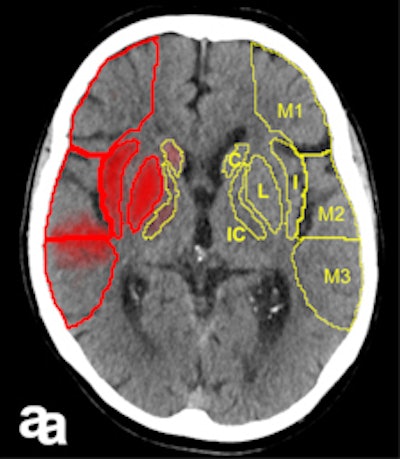

In large clinical studies, thrombectomy has been used mainly in patients whose CTs show a lower degree of severity, normally assessed using the Alberta Stroke Program Early CT Score (ASPECTS). In most of the successful studies, including ESCAPE, SWIFT PRIME, and REVASCAT, the ASPECTS must be no worse than six or seven points out of 10.

ASPECTS scoring is standard in patients who undergo CT for a recent stroke. "Doing the scores manually requires a high degree of experience, and is prone to error," Herweh said, adding that this problem can be solved by using software to calculate the scores. "It's more objective, and may be better than radiologists at evaluating patients' prognoses."

The Brainomix eASPECTS software, which has been around for some time now, is increasingly proving its value in clinical studies.

An initial validation study of 34 patients by the Heidelberg group showed that software evaluation of CT images was better than assessments by radiologists with limited training, and performed to the same level as experts. Furthermore, a U.K. study of 132 patients showed the software was at least equal to neuroradiologists, he explained.

It works from a technical viewpoint, but the key clinical question is whether this method is better than, or as good as, experts at predicting which patients have a poor prognosis. Therefore, Herweh and his colleagues carried out a third study of 212 recent stroke patients, using three experts and the software to calculate the ASPECTS retrospectively. The result was then correlated with the patients' actual clinical progress.

"What we've shown is that the software reliably predicts a poor prognosis following thrombectomy," he stated.

A low eASPECTS has a statistically significant correlation to such a prognosis. Among experts, however, this correlation was statistically significant in only one out of three cases. In other words, software-based scoring could be more objective and clinically conclusive than manual scoring by experts.